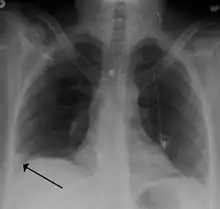

Pulmonary embolism (white arrow) that has been long-standing and has caused a lung infarction (black arrow) seen as a reverse halo sign.

- Chest X-rays are often done on people with shortness of breath to help rule-out other causes, such as congestive heart failure and rib fracture. Chest X-rays in PE are rarely normal,[67] but usually lack signs that suggest the diagnosis of PE (for example, Westermark sign, Hampton's hump).